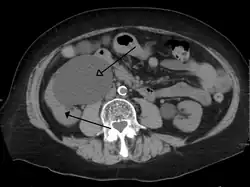

-

Stone causing hydronephrosis[16]

Urine jets[16]